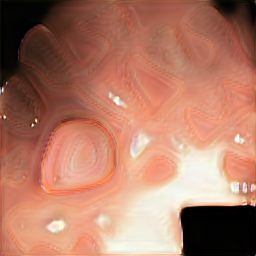

A few sample images and the corresponding masks of the polyp dataset in HyperKvasir are shown in Fig 2. The polyp images are RGB images. The masks of the polyp images are single-channel images with white () for true pixels, which represent polyp regions, and black () for false pixels, which represent clean colon or background regions. In this dataset, there are different sizes of polyps. The distribution of polyp sizes as a percentage of the full image size is presented in the histogram plot in Fig 3, and we can observe that there are more relatively small polyps compared to larger polyps. Additionally, a subset of this dataset was used to prove that the performance of segmentation models trained with small datasets can be improved using our SinGAN-Seg pipeline, and the whole dataset was used to show the effect of using SinGAN-Seg generated synthetic images instead of a large dataset which has enough data to train segmentation models. In this regard, this dataset was used for two purposes:

After training SinGAN-Seg models, we generated random samples per real image using the input scale , which is the lowest scale that uses a random noise input instead of a re-scaled input image. For more details about these scaling numbers and corresponding output behaviors, please refer to the vanilla SinGAN paper [56]. Three randomly selected training images and the corresponding first synthetic images generated using scale are depicted in Fig 4. The first column of the figure represents the real images and the ground truth mask annotated from experts. The rest of the columns represent randomly generated synthetic images and the corresponding generated mask.